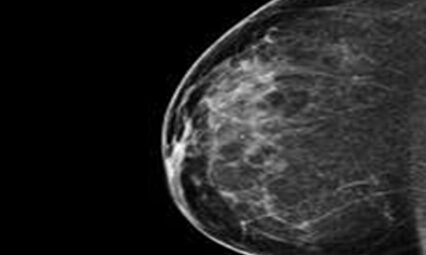

WHAT IS MAMMOGRAPHY?

Mammography is specialized medical imaging that uses a low-dose X-ray system to see inside the breasts. A mammography exam, called a mammogram, aids in the early detection and diagnosis of breast diseases in women.